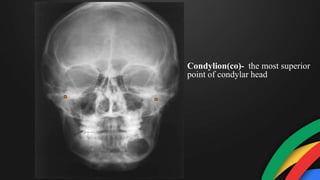

Condylion(co)- the most superior

point of condylar head

Condylion(co)- the mostsuperior point of condylar head